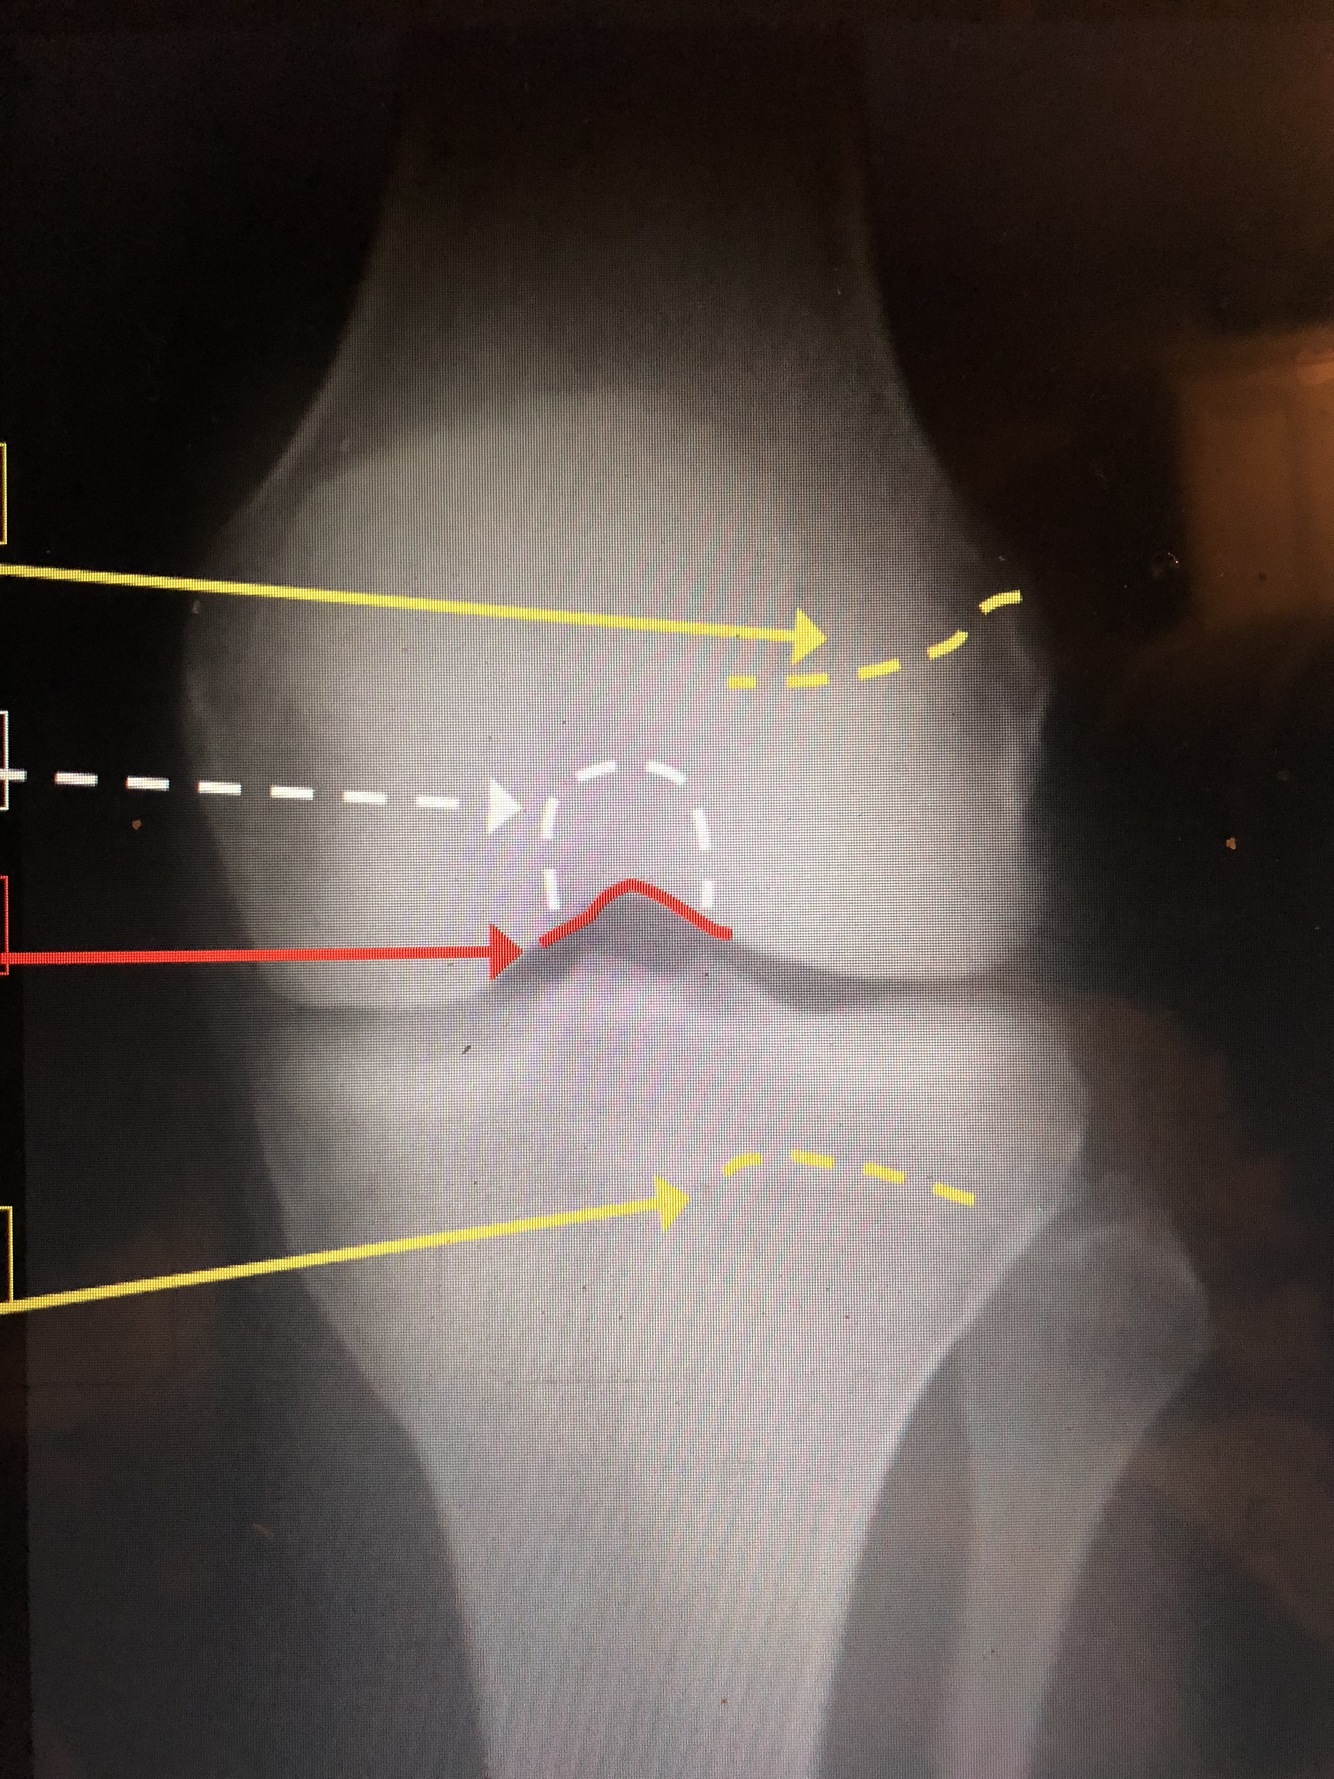

What is the top yellow dotted line?

Femoral Physeal Scar

What is the bottom yellow dotted line?

Tibial Physeal Scar

What is the white dotted line?

Intercondylar Fossa

What is the red line?

Intercondylar Notch